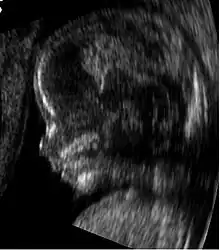

L’échographie (2) d'un embryon de 14 semaines.

- Image qui en découle.

Vous voulez savoir le sexe de votre bébé ? Il est visible sur l’échographie.